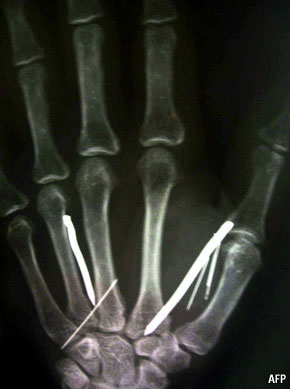

رغم كون الحالة التي ظهرت مؤخراً في السعودية و هي قيام رب أسرة سعودية و زوجته بدق أكثر من 24 مسمار في جسد مستخدمة لديهم في المنزل من أكثر الحالات وحشية إلا أن المعاملة القاسية للخدم في منطقة الشرق الأوسط شائعة عموماً.